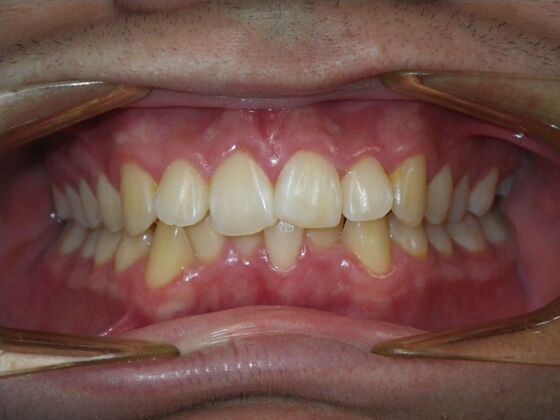

Patient presents with constricted upper and lower arches that will need expansion as well as slenderizing (IPR) to correct upper and lower anterior crowding.